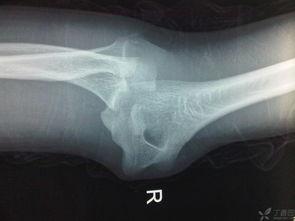

1. 观察肘关节情况:首先,仔细观察孩子的肘关节,确定是否真的发生了脱位。